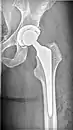

| X-ray of hip with femoral head osteonecrosis | |